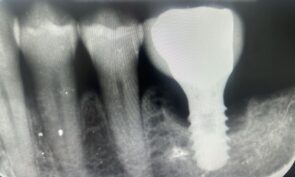

Hieronder laten we een perfecte casus zien van een verontreinigd implantaatoppervlak dat is glad gemaakt met behulp van NiTi brushes en Perisolv. Daarna is er opgebouwd met hyaluronzuur, smartgraft en een membraan. Tot slot heeft de behandelaar het geheel twee maanden laten genezen met een healing abutment. De resultaten op de foto's hieronder spreken voor zich.